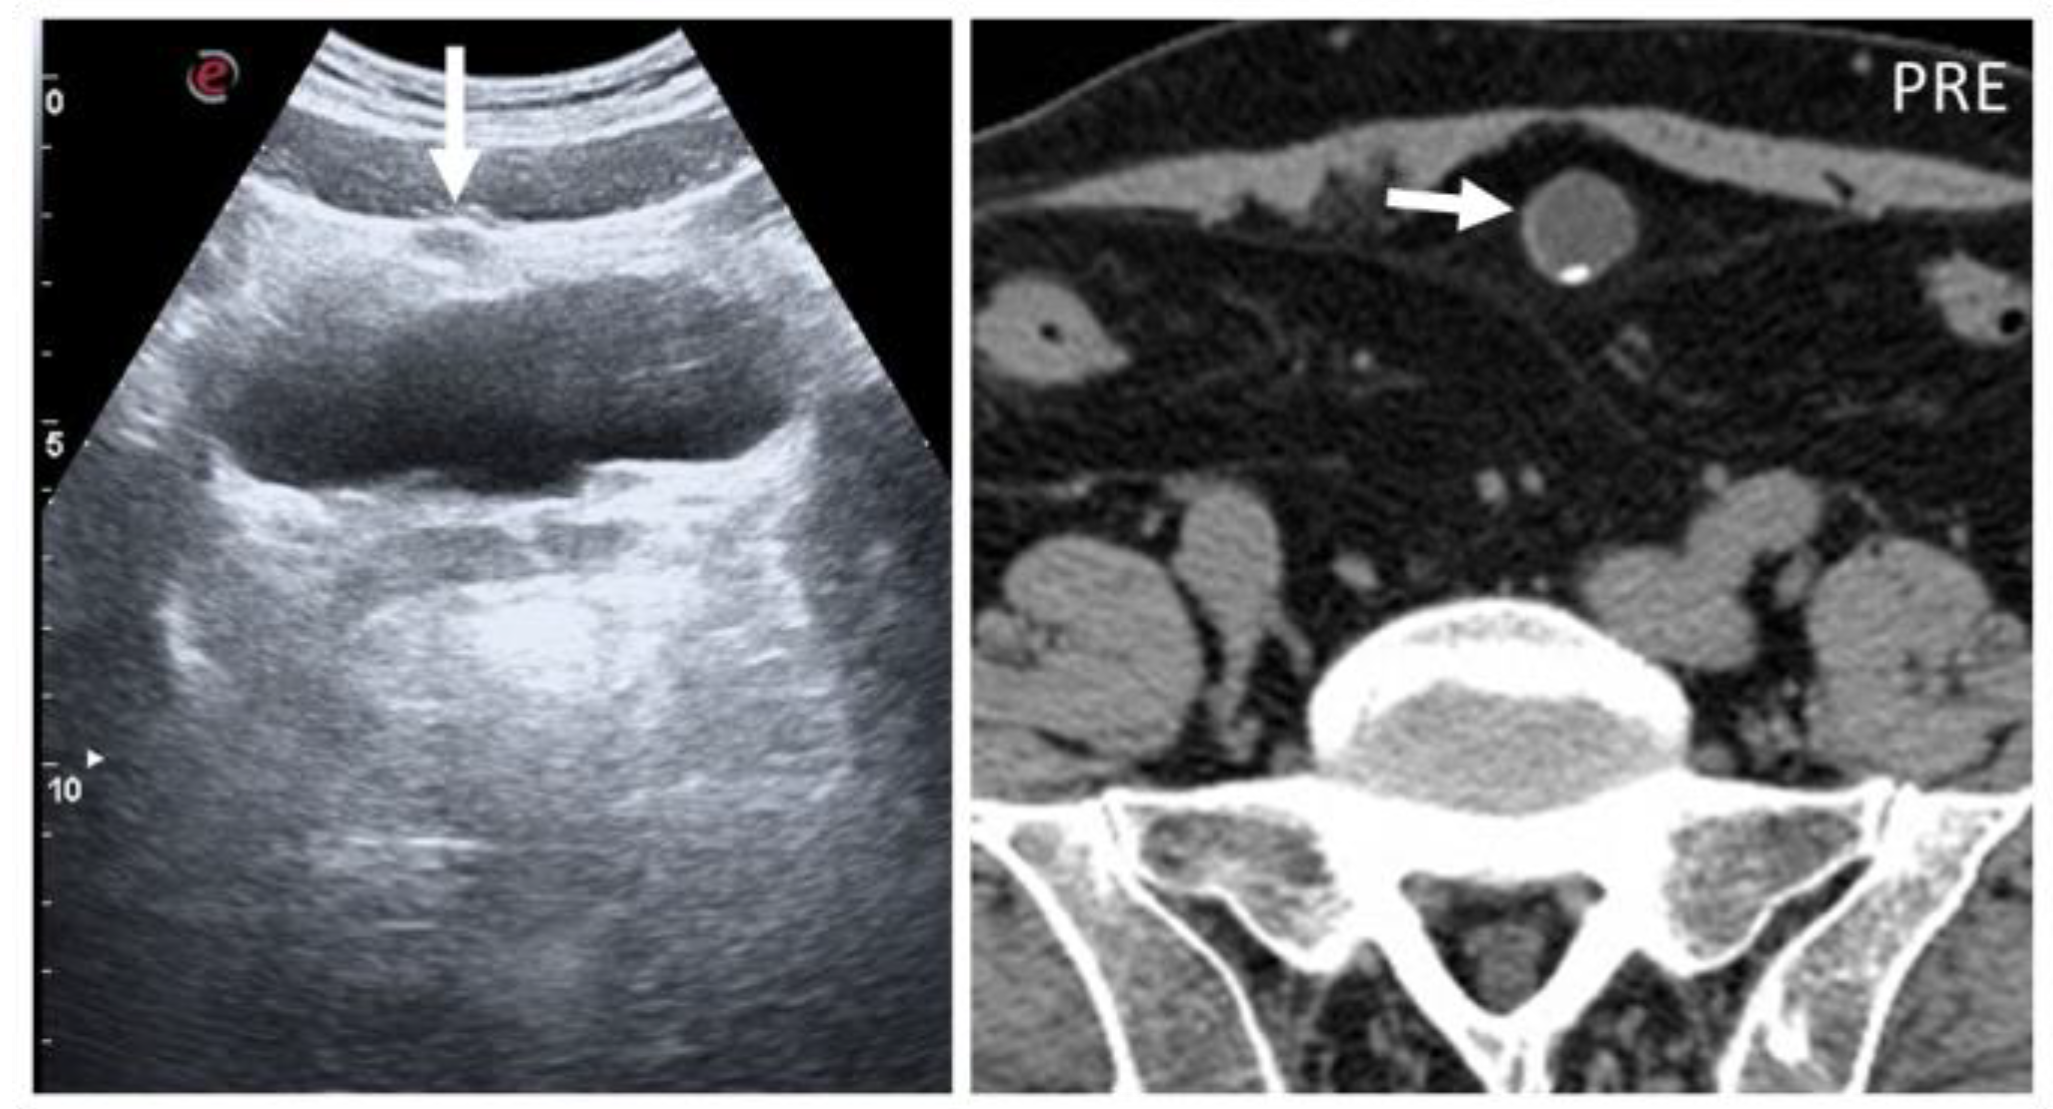

5.5. Splenosis